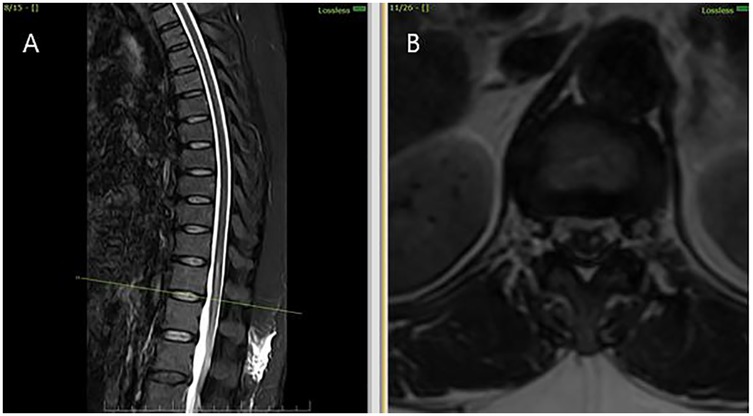

Figure 1

MRI scans showing spinal images: Panel A displays a sagittal view of the spine with detailed vertebrae and spinal cord alignment. Panel B presents an axial view of the spine, focusing on the cross-sectional anatomy.

Figure 1. MRI thoracolumbar spine findings suggestive of sulcal artery infarction. (A) Sagittal T2-weighted MRI shows a linear hyperintense lesion in the anterior portion of the spinal cord at the D12 -L1 level, with no evidence of compressive pathology. (B) Axial T2-weighted MRI at the D12- L1 level demonstrates hyperintensity involving the anterior horn and intermediate zone of the left hemicord, consistent with sulcal artery territory infarction.

MRI findings further corroborated the clinical suspicion: there was T2 hyperintensity predominantly involving the anterior horn and intermediate zone of the left hemicord at D12- L1 vertebral level without enhancement or mass effect. In the absence of compressive or infectious causes, the radiologic diagnosis of non-traumatic spinal cord infarct is strongly supported.